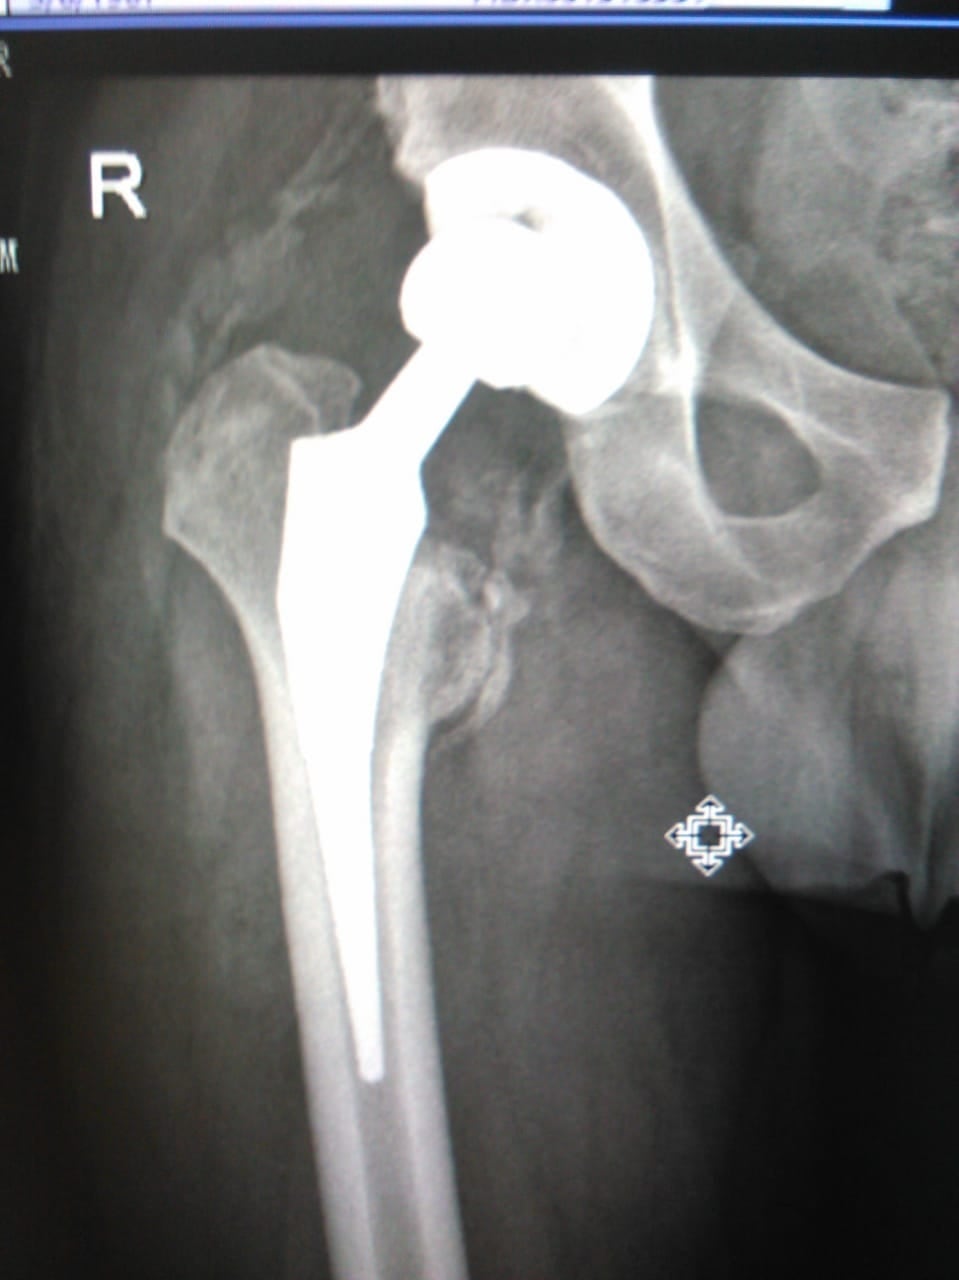

Según el tráfico, la parte redonda del fémur que se conecta con la cadera se dañó por completo al salirse de su lugar, motivo por el cual tuvo que ser llevado de emergencia al hospital de Guápiles.

Le lesión fue tan grave que el tráfico tuvo que ser llevado al Hospital del Trauma, en La Uruca, donde le realizaron una delicada operación en la cadera para ponerle una placa de metal y reconstruir el hueso de su pierna.